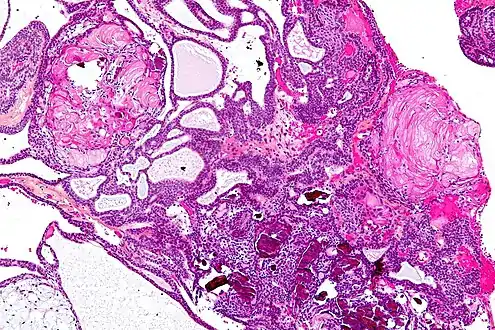

The papillary type rarely calcifies. A vast majority of craniopharyngiomas in children are adamantinomatous, whereas both subtypes are common in adults. Mixed-type tumors also occur.[25]

On macroscopic examination, craniopharyngiomas are cystic or partially cystic with solid areas. On light microscopy, the cysts are seen to be lined by stratified squamous epithelium. Keratin pearls may also be seen. The cysts are usually filled with a yellow, viscous fluid rich in cholesterol crystals. Of a long list of possible symptoms, the most common presentations include headaches, growth failure, and bitemporal hemianopsia.

Micrograph showing a papillary craniopharyngioma, HPS stain